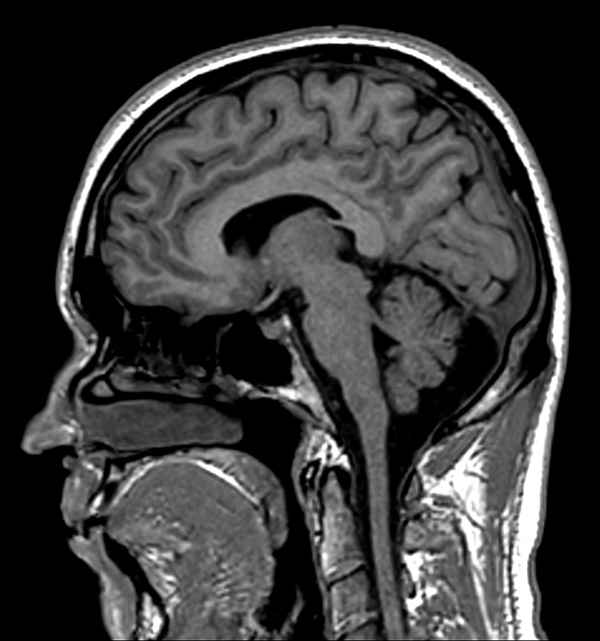

Comprehensive Brain imaging at 1.5T

Used Solution